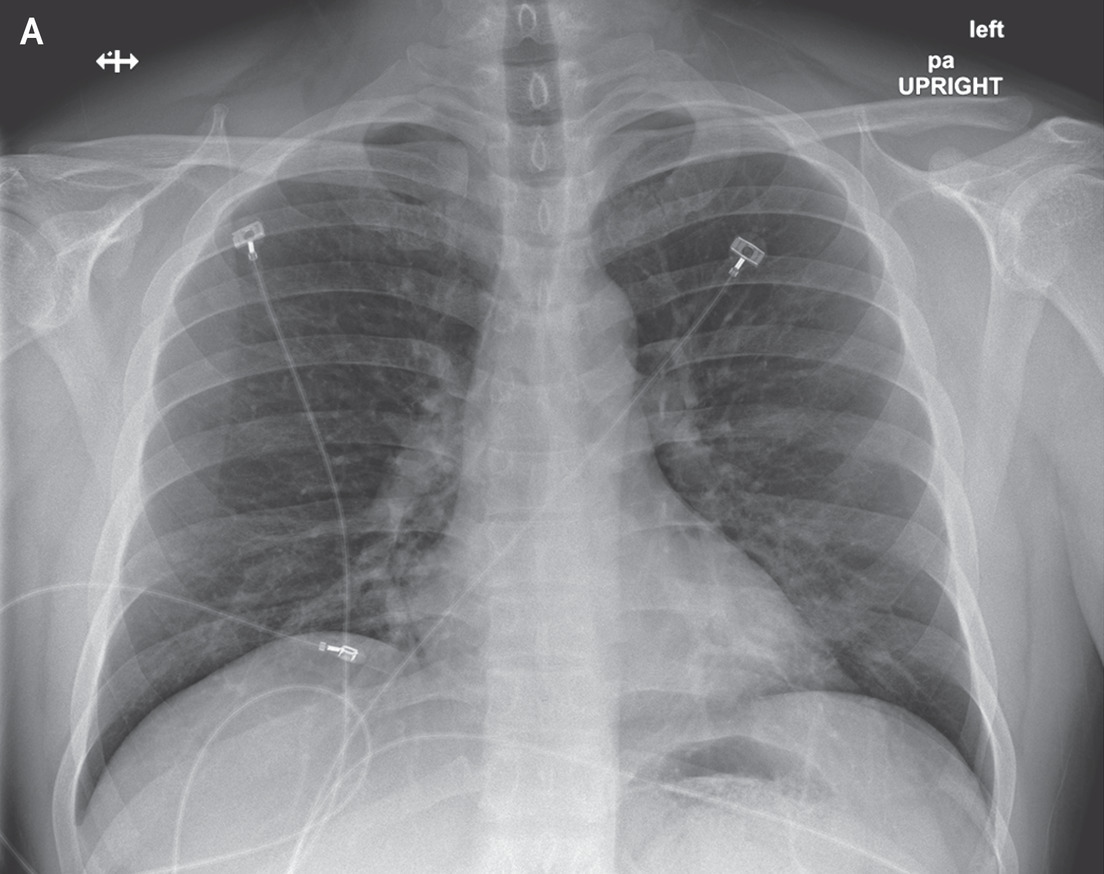

All our experiments use five-fold cross-validation to split target class. To compose the complete test set we use the fold used as a test, together with all the outliers samples. Finally, we repeat the approach twenty times taking means and variance to compare our results with other models. In our experiments we use six numerical datasets from UCI repository (see. Table. 5) and a novel dataset of Covid-19 that contains chest X-ray or CT images of positive/negative patients (see Fig. 1). In order to have the right comparison criterion in Covid-19 dataset, we extract confusion matrix as reported in Tab. 4 and compute the precision metric described in Eqs. 13 and 14. These last measures are needed to compare the class accuracy of the proposed OCdmst and the Resnet18 used in our experiments.

In the third experiment, we demonstrate by experimental results the effectiveness of our model with few data and compare it with a neural network (Resnet18). We simulate the scenario in which we have too few data to deny common neural networks to make right discrimination of different concepts (two classes in our case). Therefore we apply a 2-Fold cross-validation considering all data available from Covid-19 dataset and we extract the deep features for each model trained (Resnet18). All images have been re-scaled to 256x256 pixels and transformed to gray-scale. Learning rate and batch-size are set to 0.001 and 10 respectively. As evaluation metric we do not consider the total accuracy but we evaluate the accuracy for each class (Precision). Then, we use the deep features as input to our OCdmst using the dataset split in the previous step. The results reported in Tab. 2 show the flexibility of our model to operate also with

Resnet18 learned features using cross-entropy loss. As showed in Tab. 2, Resnet18 does not offer right prediction to recognize instances from negative class. This results is reasonable considering we have too few data with negative labels. Even when we used features extracted by Resnet18 to our model, but OCdmst is able to recognize value from both classes and overcome the right prediction also on positive class. The confusion matrix showed in Fig. 7 and accuracies for each class demonstrate the capability of OCdmst to operate also in a scenario with few data, as well as overcome deep neural networks. This last result is plausible because it represents one of the weaknesses of deep models.